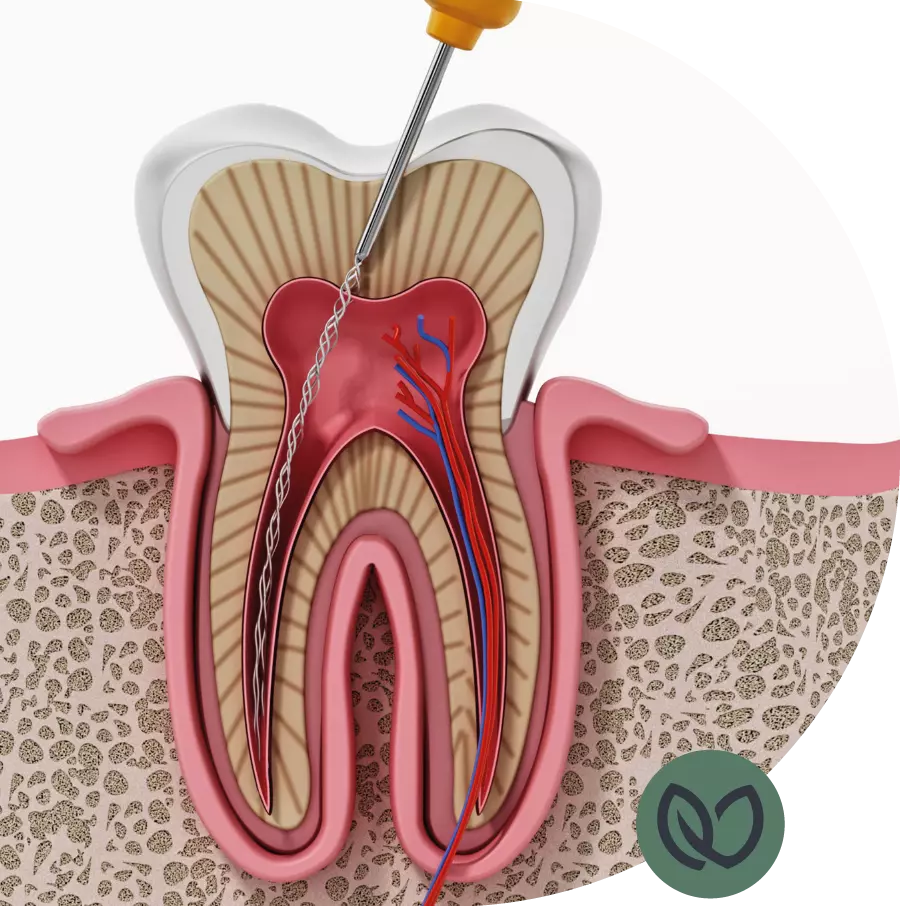

A root canal treatment is usually necessary when the tooth nerve becomes infected or inflamed. This can occur due to deep tooth decay, tooth trauma, a cracked tooth, or a leaking filling. The symptoms of an infected tooth can vary but may include persistent pain, sensitivity while chewing, gum swelling, or tooth discoloration.

An inflamed tooth nerve can cause severe pain and discomfort. Moreover, the infection can spread to surrounding tissues and other teeth. It is important to remove inflammation from the body, even if it doesn’t always cause pain. An untreated infection can lead to more serious health issues and damage to the dentition. A root canal treatment provides an effective solution to address the problem at its source and restore your oral health.

The number of root canals in a tooth varies depending on its location. A front tooth usually has one canal, while a molar or premolar can have multiple canals. This is important to know as it can affect the complexity of the treatment. Our experienced dentists are well-trained and have expertise in locating and cleaning all canals, regardless of the number.